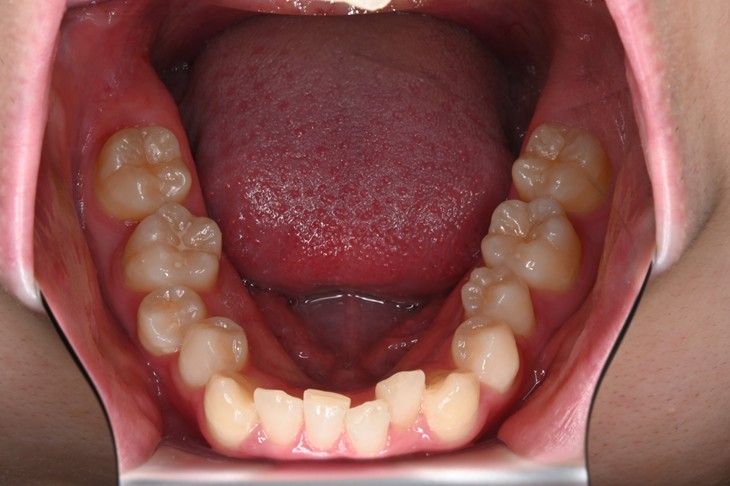

症例2:八重歯が気になる

| 患者様データ | 20代 女性 |

| 来院主訴 | 八重歯が気になる。 |

| 治療内容 | 八重歯を治すために上の親知らずを抜歯し、インビザラインにてマウスピース矯正を開始しました。かみ合わせを整えるためにゴムかけを行いました。 |

| 概算治療費 | 約85万円 |

| 治療期間 | 1年3ヶ月 |

| 通院回数 | 8回 |